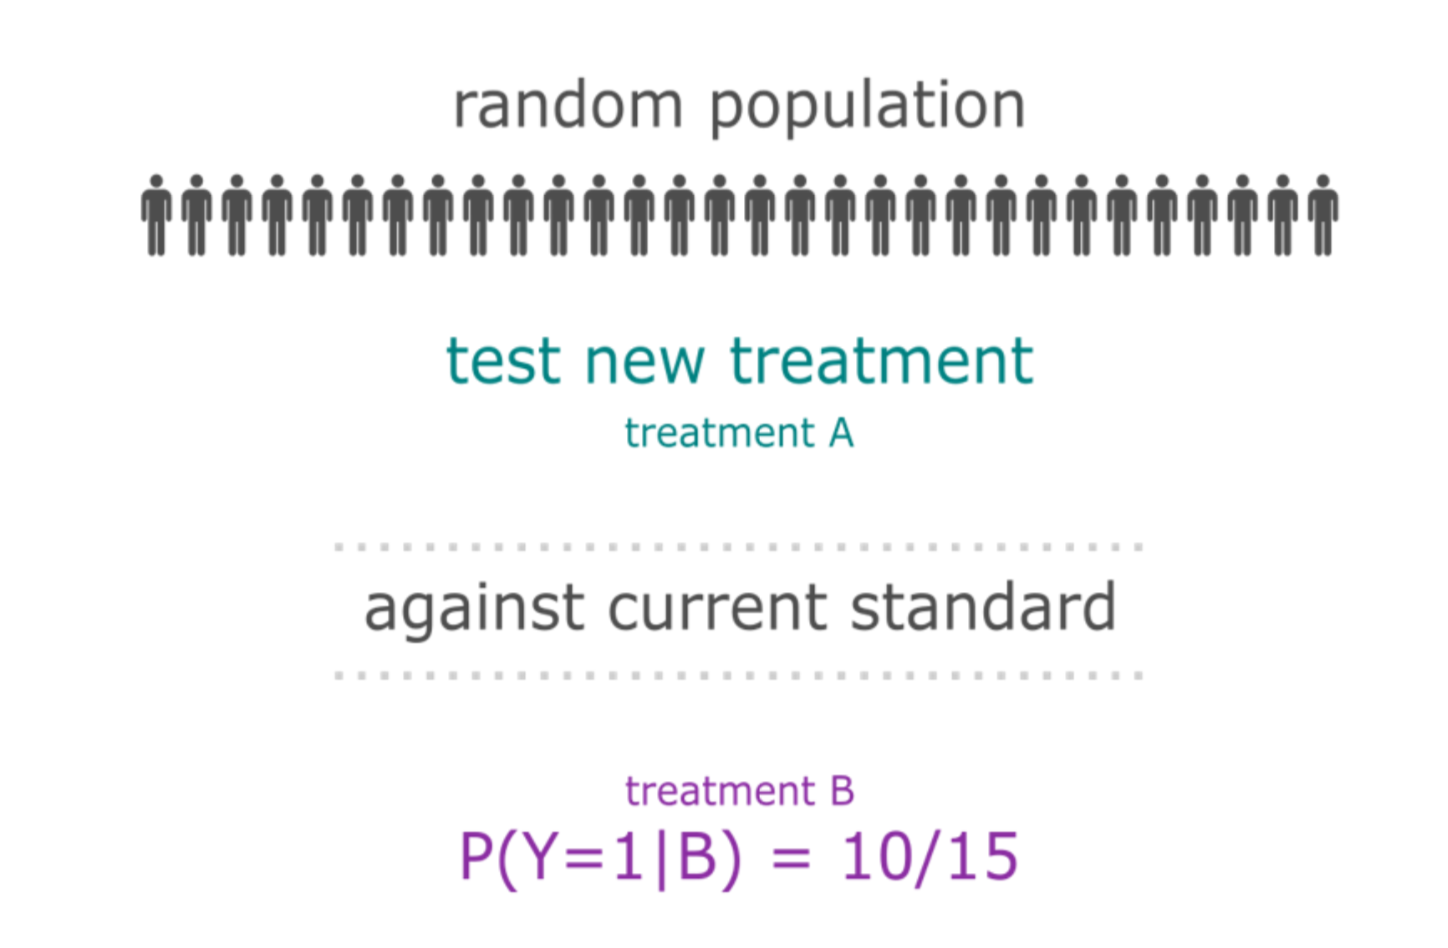

The "old" way of conducting clinical trials

New compound is developed and is thought to deliver a (small) benefit over current therapies for a specific histology

A large number of patients are enrolled (at least hundreds)

The response rate of the treatment population is tested against a control group